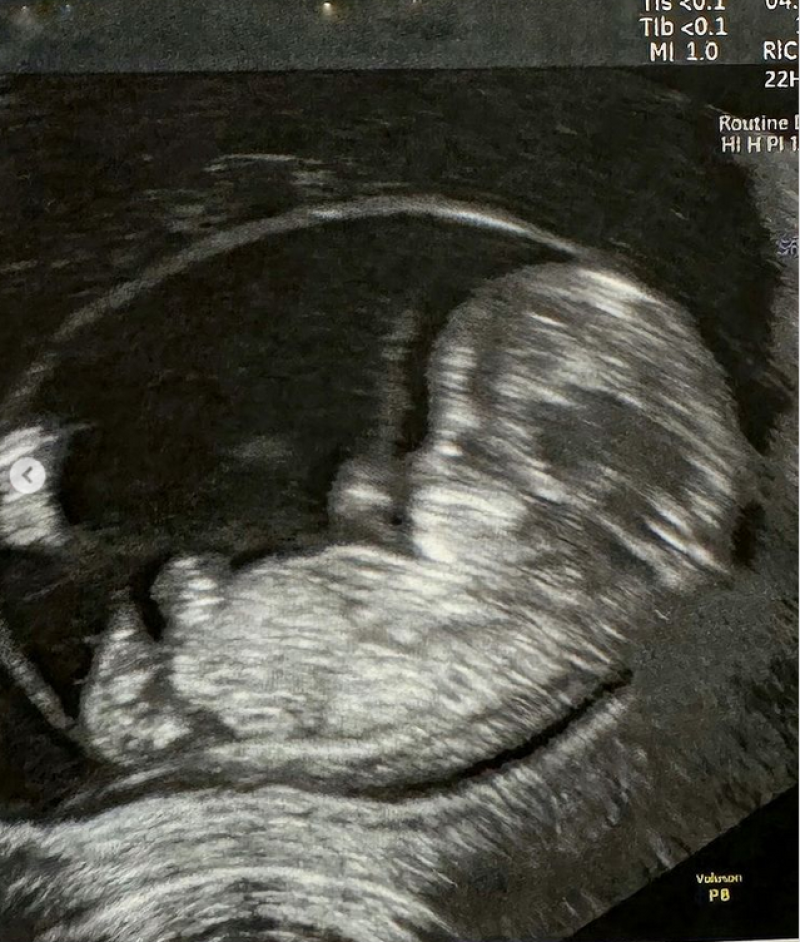

“ถึงเวลาที่พอจะบอกทุกคนได้แล้วค่ะ ช่วงเกือบ 2 เดือนที่ผ่านมาที่ไม่ได้ไปอ่านข่าวใส่ไข่และตลาดสด เพราะว่าต้องดูแลลูก ทั้งน้องคิดและประคองอีกหนึ่งชีวิตในท้อง เนื่องจากรถเมล์มีภาวะแท้งคุกคาม เย็นนี้จะกลับไปอ่านข่าวแล้วค่ะไว้จะเล่าให้ฟังในข่าวใส่ไข่นะคะ Soon to be family of4. KIDD leveled up to big brother

ตั้งท้องลูกคนที่ 2